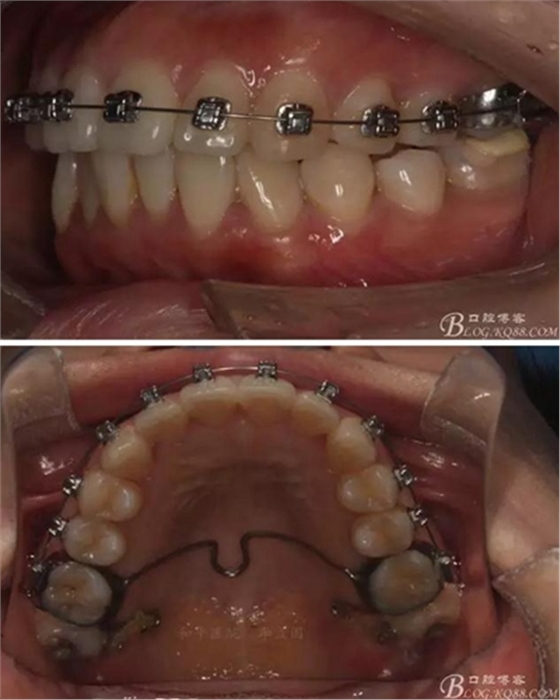

患者,女,主訴:牙齒不齊。

如圖,該病例為簡單排齊病例,但77鎖合是矯治中的關(guān)鍵所在,你會怎么處理?

該病例主要為17、27頰側(cè)位同時伴有伸長,當(dāng)然種植支抗可以解決,但還有簡單實(shí)用的辦法嗎?如圖,在橫腭桿遠(yuǎn)中延伸出牽引鉤,位置盡量遠(yuǎn)離合平面,7粘舌側(cè)扣,牽引力的方向?yàn)閴旱图吧嘞?,下圖為兩個月的效果,17已到位,27還未到位。